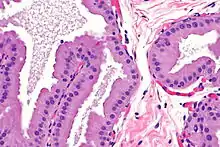

Apocrine metaplasia is a reversible transformation of cells to an apocrine phenotype. It is common in the breast in the context of fibrocystic change. It is seen in women mostly over the age of 50 years. Metaplasia happens when there is an irritation to the breast (breast cyst). Apocrine-like cells form in a lining of developing microcysts, due to the pressure buildup within the lumen. The pressure build up is caused by secretions.[4] This type of metaplasia represents an exception to the common rule of metaplasia increasing the risk for developing cancer in that apocrine metaplasia doesn't increase the possibility of developing breast cancer.[5]